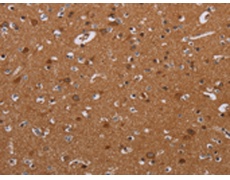

IHC positive control: |

Human brain and Human esophagus cancer |

IHC Recommend dilution: |

25-100 |